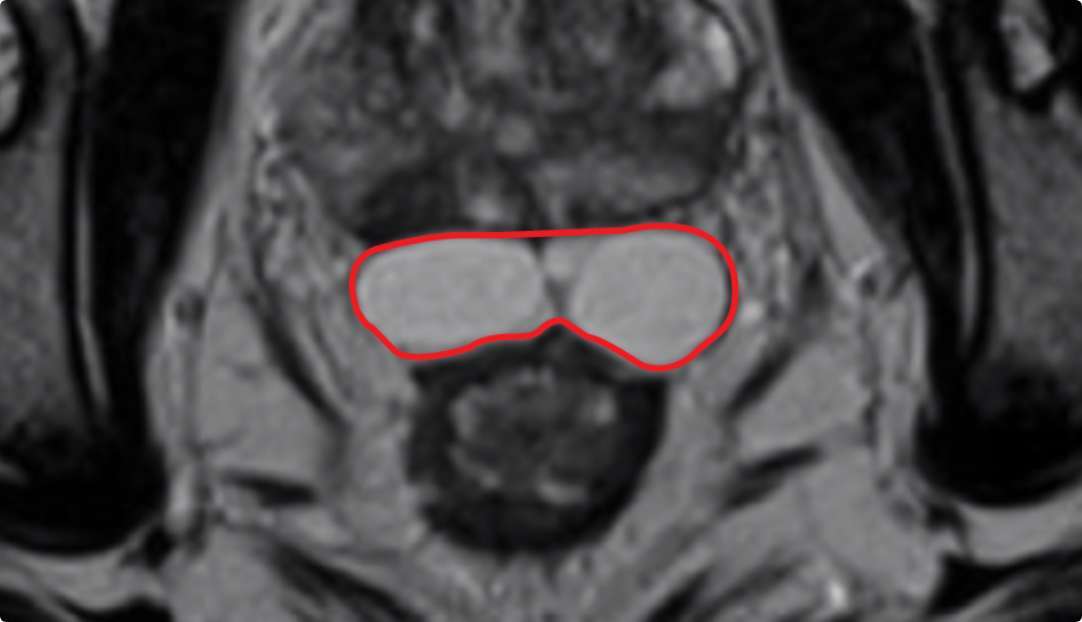

Implant Symmetry RESULTS6 >95%

Pivotal Trial Patients; % of implants centered on prostate midline

PEG HYDROGEL

Implant Symmetry RESULTS7 >49%

First Barrigel Cases - Consecutive Patients (Same Day)

TRUS images courtesy of Daniel R. Welchons, MD

Urologist; New York, United States